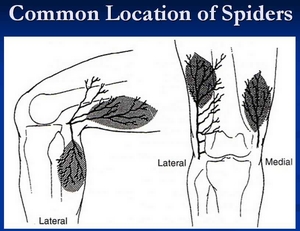

靜脈曲張的外觀可見扭曲, 鼓漲, 顏色深藍, 大小不規則的血管, 非常靠近皮膚表面, 所以很明顯, 像蜘蛛爬在腳上, 好聽一點的說法, 就像葡萄結實在果樹上(thread veins or spider veins or dermal flares), 這其實已經象徵靜脈功能不全(venous insufficiency).由於靜脈太靠近表皮, 使得皮膚會產生問題, 如濕疹(eczema)或潰瘍(ulcer)的發生, 當然這是嚴重, 或是不理會它, 任由它作惡加重的情況. 更嚴重的人, 還發生過出血, 需要緊急止血; 或是發炎, 導致靜脈血栓的惡劣併發症, 所以不可以置之不理.

(5) Laser (雷射)

針對非常表面與微小的蜘蛛網狀靜脈血管, 利用雷射穿透皮膚不留疤痕的優點, 來消除難看的藍色血管異常.